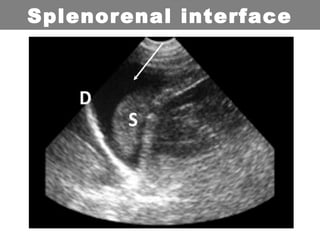

Scans are obtained at 4 interfaces:

•Splenorenal interface

Splenorenal interface